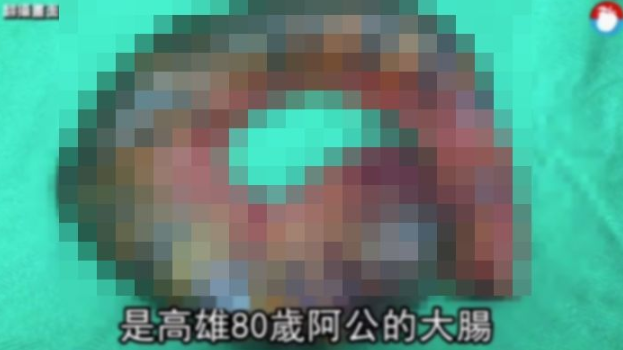

そのため医師はすぐにおじいさんを手術室に運び手術を行いました。驚くことに、手術の過程でおじいさんは真っ黒に壊死してしまった腸を、なんとおおよそ30cmも除去する必要があると宣告されました。

手術直後、医師は「腸内の健康な人は、通常ピンクがかっている」とし「このおじいさんの場合、一週間もの間、腸から大便が抜け出せなかったため、腸が真っ黒に変わり果ててしまい、除去するしか方法はなかった」と述べました。